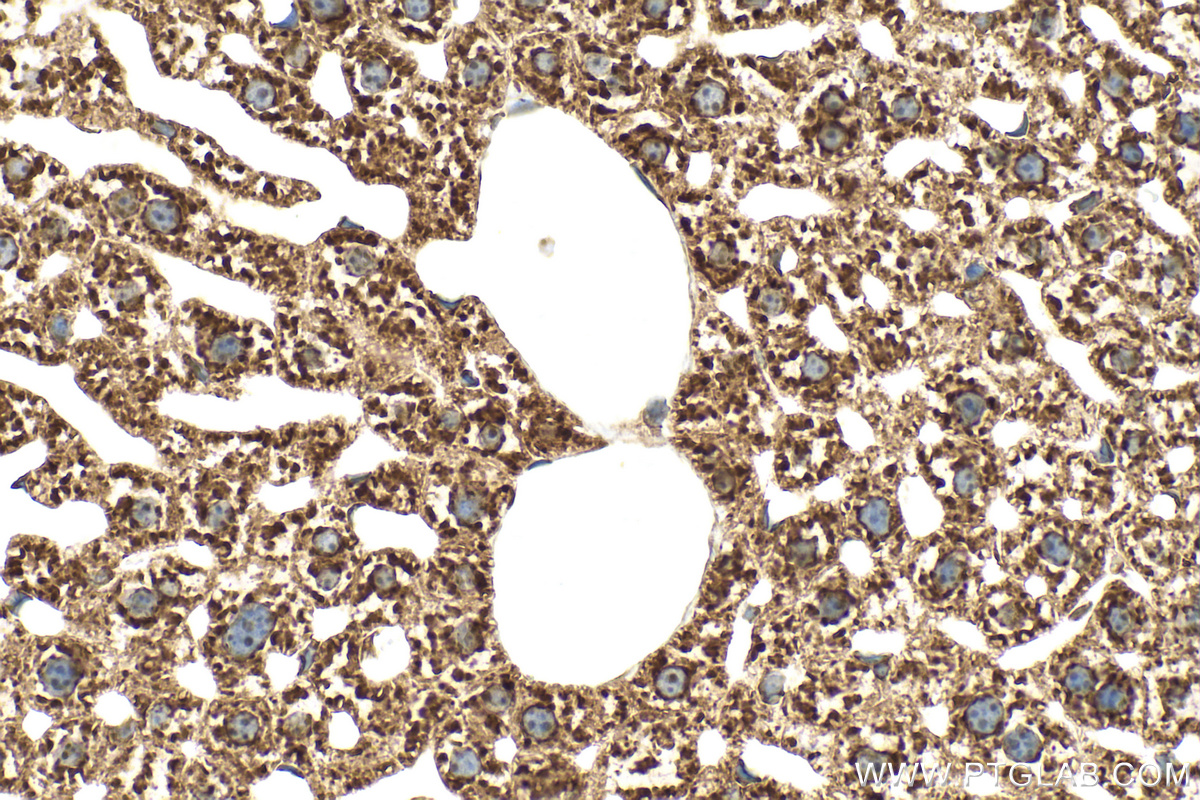

| Positive IHC detected in | mouse liver tissue Note: suggested antigen retrieval with TE buffer pH 9.0; (*) Alternatively, antigen retrieval may be performed with citrate buffer pH 6.0 |

| Immunohistochemistry (IHC) | IHC : 1:250-1:1000 |